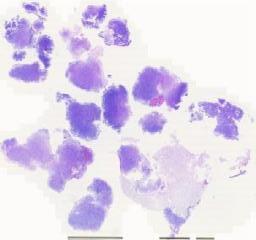

临床资料: 男性,39岁,右侧基底节区占位 主诉:左侧肢体麻木伴持物及行走不稳20余天,加重1周。 体征:肌力下降:左上肢II级,左下肢II级。余未见特殊。 头颅MRI:右侧基底节区、侧脑室旁及半卵圆中心囊实性、实性占位。 术中所见:术中B超见病变位于右基底节区,累及内囊后肢,病变周围的脑回肿胀,脑沟变浅。术中皮层下1.5cm见可疑肿瘤组织,呈灰白和灰红色相间,质韧,无包膜,血运丰富,浸润性生长,与周围正常脑组织无明确界限,局部可见血肿。

大体所见: 送检灰白色组织,共大约3.5 ×3.0 ×1.8cm,切面灰白色,质地中等。